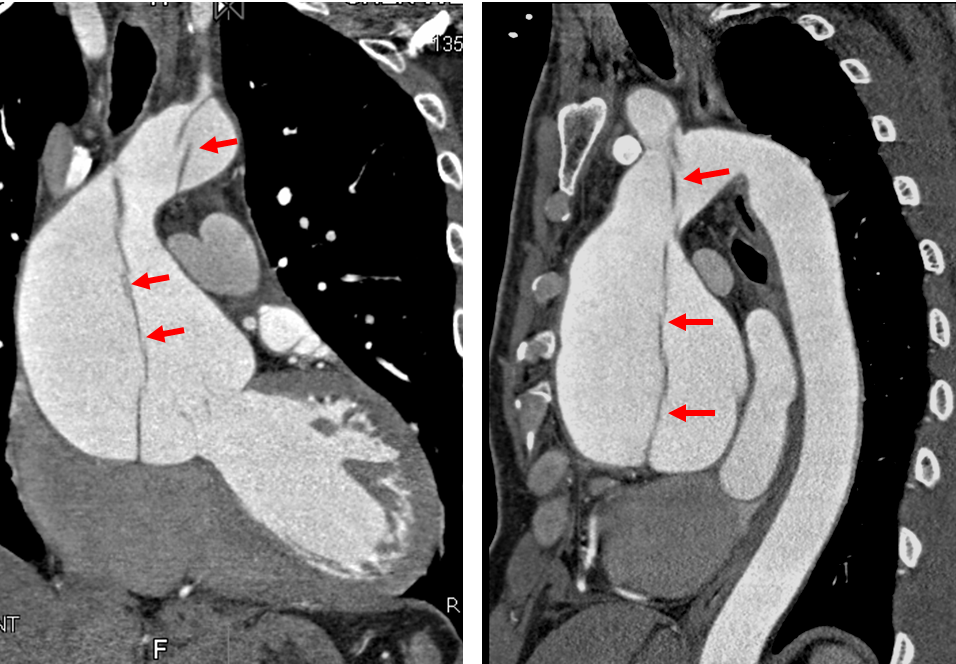

●案例一:40歲男性罹患主動脈剝離,冠狀動脈攝影電腦斷層影像顯示升主動脈擴大,直徑約82.2mm,主動脈內膜剝離(箭頭)至主動脈弓,幸好冠狀動脈未受影響。文獻統計主動脈剝離患者3%立即死亡,20%~30%在24小時內死亡。